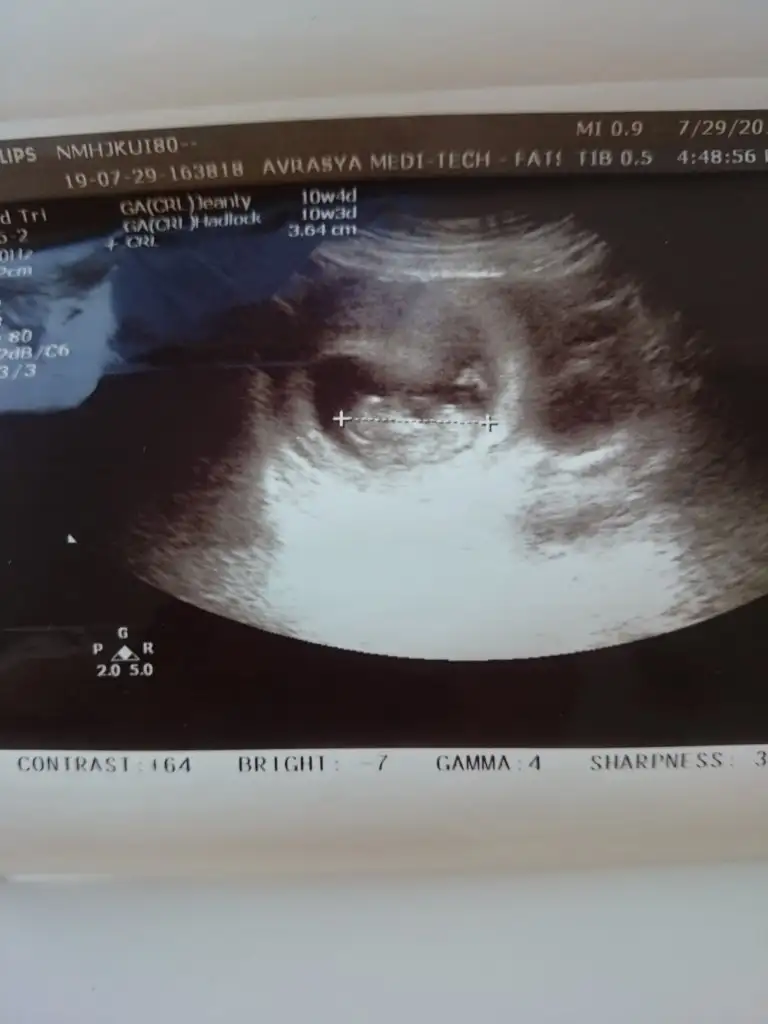

Bana da tahmin de buluabilir misiniz? :KK36: daha küçük ama